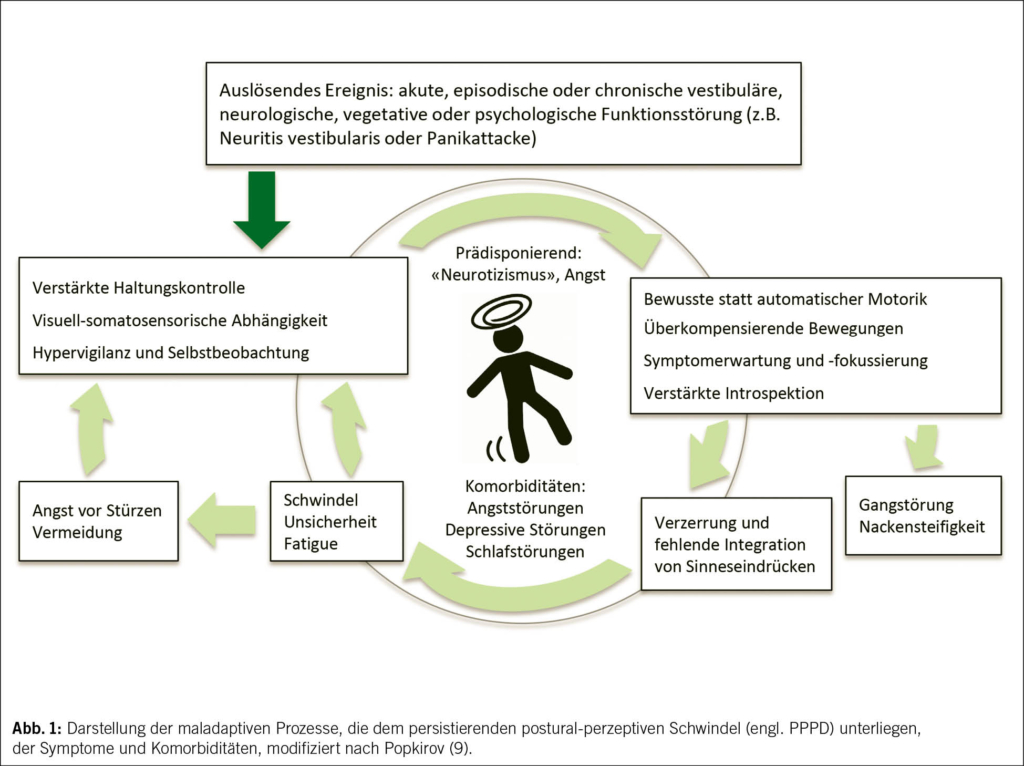

Schädigungsmuster und klinische Bedeutung des R-Werts

Zur weiteren Einordnung hat sich die Bestimmung des R-Werts etabliert, berechnet aus dem Verhältnis ALT/ULN zu ALP/ULN. Er erlaubt die Einteilung in hepatozelluläre (R ≥ 5), cholestatische (R ≤ 2) und gemischte Schädigungsmuster (R 2–5). Diese Klassifikation besitzt diagnostische und prognostische Relevanz. Hepatozelluläre Muster sind häufiger mit schweren Verläufen assoziiert, insbesondere bei zusätzlichem Ikterus. Cholestatische Verläufe präsentieren sich typischerweise mit Pruritus und zeigen meist einen protrahierten, insgesamt jedoch günstigeren Verlauf. Gemischte Muster vereinen Merkmale beider Entitäten. Entsprechend sollten Differenzialdiagnosen gezielt priorisiert werden, etwa virale Hepatitiden oder ischämische Leberschäden bei hepatozellulärem Muster und biliäre Obstruktionen bei cholestatischem Verlauf (7, 8). Zu beachten ist, dass einzelne Medikamente unterschiedliche Muster verursachen können. Ein strukturiertes diagnostisches Vorgehen ist in Abb. 1 dargestellt.